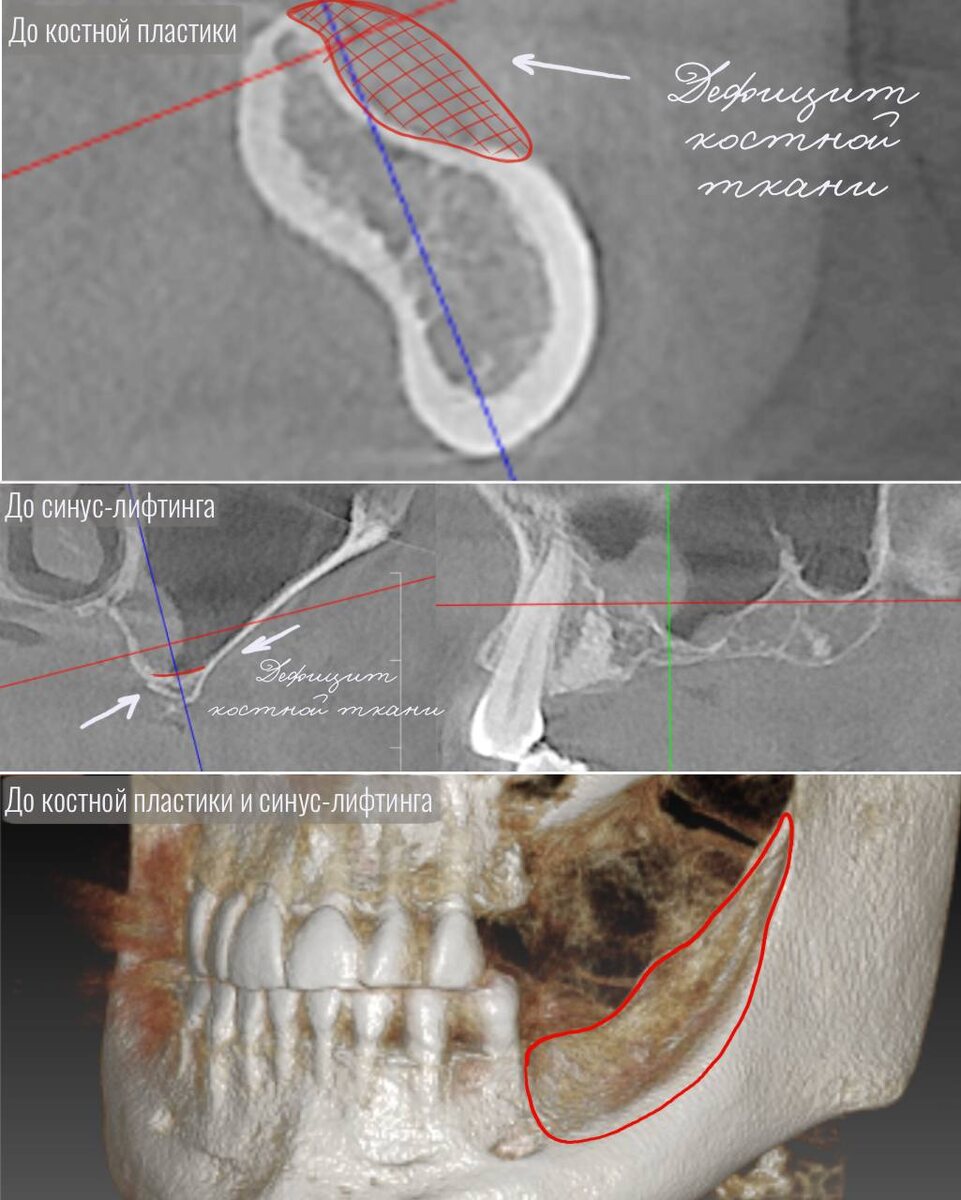

К нам обратился пациент с отсутствием жевательных зубов на левой стороне верхней и нижней челюсти. Так же наблюдался выраженный дефицит костной ткани, который делал невозможным установку имплантов без предварительного хирургического восстановления.

На нижней челюсти была проведена сложная операция костной пластики с использованием индивидуальной титановой пластины методом направленной костной регенерации (НКР). Костная пластика проводится для восстановления объёма кости на нижней челюсти, чтобы импланты могли быть надежно установлены.

Хотим отметить, что операция костной пластики была одним из самых сложных этапов! В данном случае она была нестандартной: мы использовали индивидуальную титановую пластину, адаптированную под анатомию пациента.

После установки пластины был выполнен этап направленной костной регенерации. Этот метод позволяет управлять процессом восстановления кости, стимулируя формирование новой костной ткани в нужных объёмах и формах.